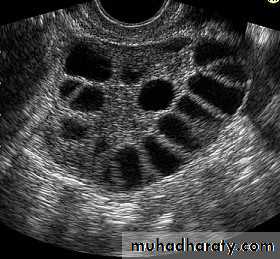

Ultrasound :

Determine the presence, state and size of ovaries and any follicular activity .

Determine the presence and size of uterus

Anovulation , e.g . polycystic ovarian syndrome

3-polycystic ovary syndrome

The other common ovarian disorder leading to anovulation and amenorrhoea is PCOSPituitary disorders